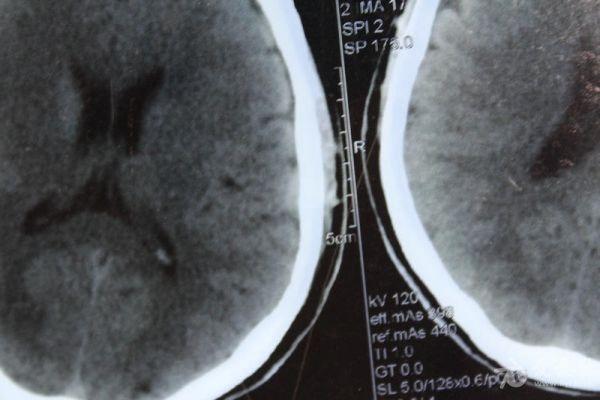

脑部占位病变CT,MRI图片,请帮忙诊断

最近感图样,无其它脑病病史

考虑脑膜瘤!!

磁共振没有平扫,增强矢状位没找到病灶。像脑膜瘤。

图片不是很清楚,应该是脑膜瘤!